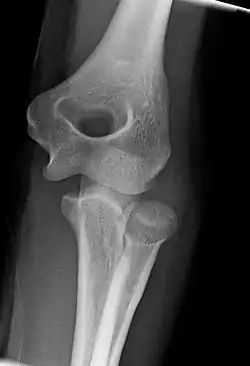

Development

The elbow undergoes dynamic development of ossification centers through infancy and adolescence, with the order of both the appearance and fusion of the apophyseal growth centers being crucial in assessment of the pediatric elbow on radiograph, in order to distinguish a traumatic fracture or apophyseal separation from normal development. The order of appearance can be understood by the mnemonic CRITOE, referring to the capitellum, radial head, internal epicondyle, trochlea, olecranon, and external epicondyle at ages 1, 3, 5, 7, 9 and 11 years. These apophyseal centers then fuse during adolescence, with the internal epicondyle and olecranon fusing last. The ages of fusion are more variable than ossification, but normally occur at 13, 15, 17, 13, 16 and 13 years, respectively.[16] In addition, the presence of a joint effusion can be inferenced by the presence of the fat pad sign, a structure that is normally physiologically present, but pathologic when elevated by fluid, and always pathologic when posterior.[17]